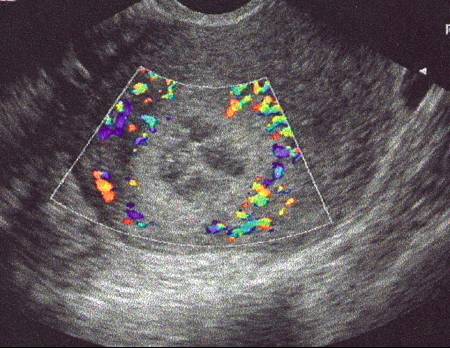

Myome en nécrobiose. Doppler couleur (Cliché : Dr. C. TALMANT)